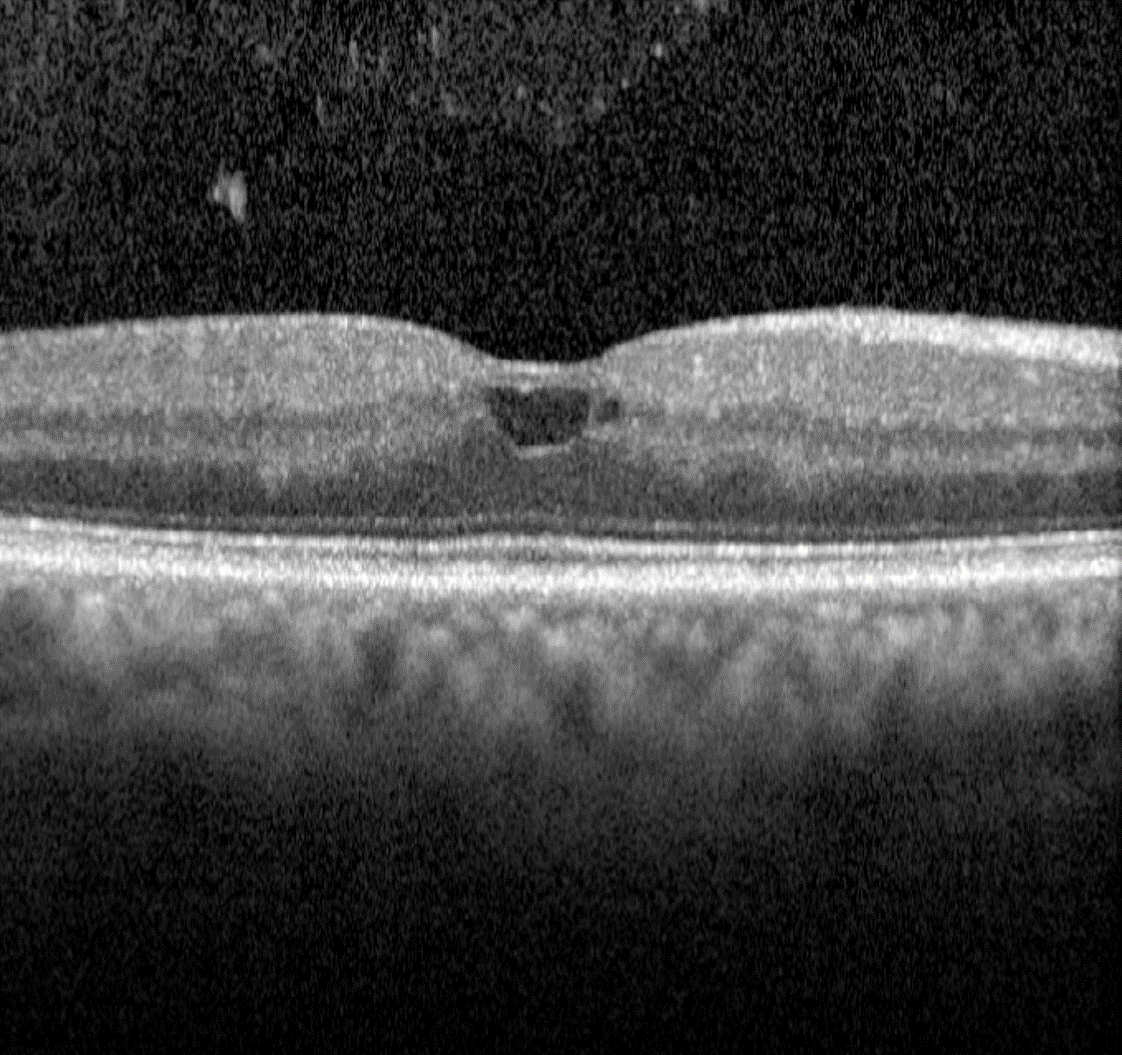

Macular Oedema

In diabetic retinopathy, macular oedema results from increased vascular permeability and a breakdown of the blood retinal barrier. These pathological processes cause leakage of lipids, proteins and serous fluid into the retina or subretinal space.

Clinical signs of macular include hard exudates and/or intraretinal oedema.

Hard exudates are discrete, yellow-white lipid deposits that may be isolated, diffuse, circinate (circular), or star-shaped. With OCT, they appear as intraretinal hyper-reflective deposits, usually in the outer plexiform layer (OPL) or outer nuclear layer (ONL). The presence of hard exudates may indicate either past or present macular oedema.

Intraretinal oedema may be appreciated clinically as retinal thickening, however can be missed in the early stages. OCT imaging may show either diffuse thickening or discrete intraretinal cystic spaces. Macular oedema may present in the absence of hard exudates, making it difficult to detect during a clinical examination or on fundus photography. For this reason, macular OCT scans are highly recommended for patients with a medical history of diabetes, particularly when other signs of diabetic retinopathy are present, macular oedema is suspected, or visual acuity is reduced.

It is important to note that hard exudates and intraretinal oedema may also be associated with other conditions, such as hypertensive retinopathy, retinal arterial macroaneurysm, Coats disease and choroidal neovascularisation.